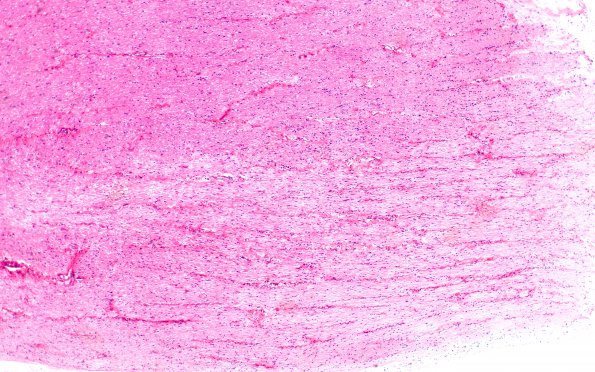

Washington University Experience | MYELIN (IMMUNE-MEDIATED) | MS - Chronic Active Plaque | 2B1 MS, (Case 2) N12 optic nerve H&E 4X

2B1-4 Classical inactive plaques in this case are typically free of significant inflammation and macrophages. ---- An optic nerve, seen longitudinally, shows pallor of myelin loss involving the lower portion of the image (H&E)